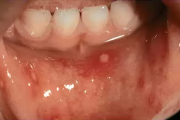

Tekitajad ja kliiniline pilt Gingivostomatiit – Tekitaja herpessimplex-viirus – Primaarinfektsioon, mille üldnähtudeks on palavik, halb enesetunne ja peavalu. – Herpeseville leidub põskede limaskestal, huultel ja keelel, sageli lõhkevad need kiiresti ja jätavad väikese erosiooni. – Loe edasi »